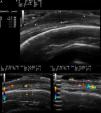

B-mode ultrasound (18MHz probe, eSaote, MyLab25Gold) showed a predominantly hypoechoic nodule of 3.7mm×16.5mm with well-defined borders, situated in the deep dermis and subcutaneous cellular tissue (Fig. 2A). The periphery of the lesion presented mixed echogenicity, in contrast to the more hypoechoic central area. In the deep region of the lesions was a hyperechoic area that may have been posterior enhancement. The epidermis appeared as a hyperechoic band. The lesion extended diffusely peripherally, and it was more difficult to identify its borders in this plane (Fig. 2, B andC). At the lateral borders of the lesion and in the non-nodular part of the tumor, areas of mixed echogenicity predominated over the hypoechoic areas. Color Doppler showed an irregular asymmetric neovascularization at the periphery of the lesion (Fig. 2, B andC).

A, Hypoechoic nodule with well-defined borders that are slightly more echogenic than the center of the nodule. B, Color Doppler showed increased vascularity and asymmetrically distributed medium-sized vessels in the base of the nodule. C, Increased vascularity in the non-nodular area of the lesion.